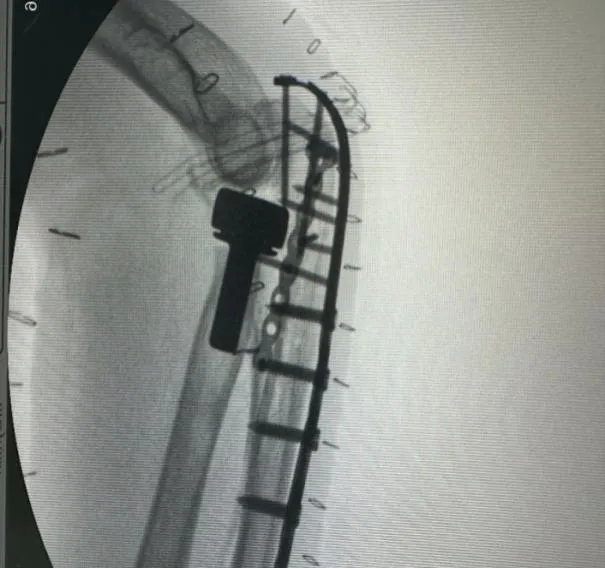

王女士外院手法复位后拍片示左肘关节半脱位

图片

▲左肘关节术前